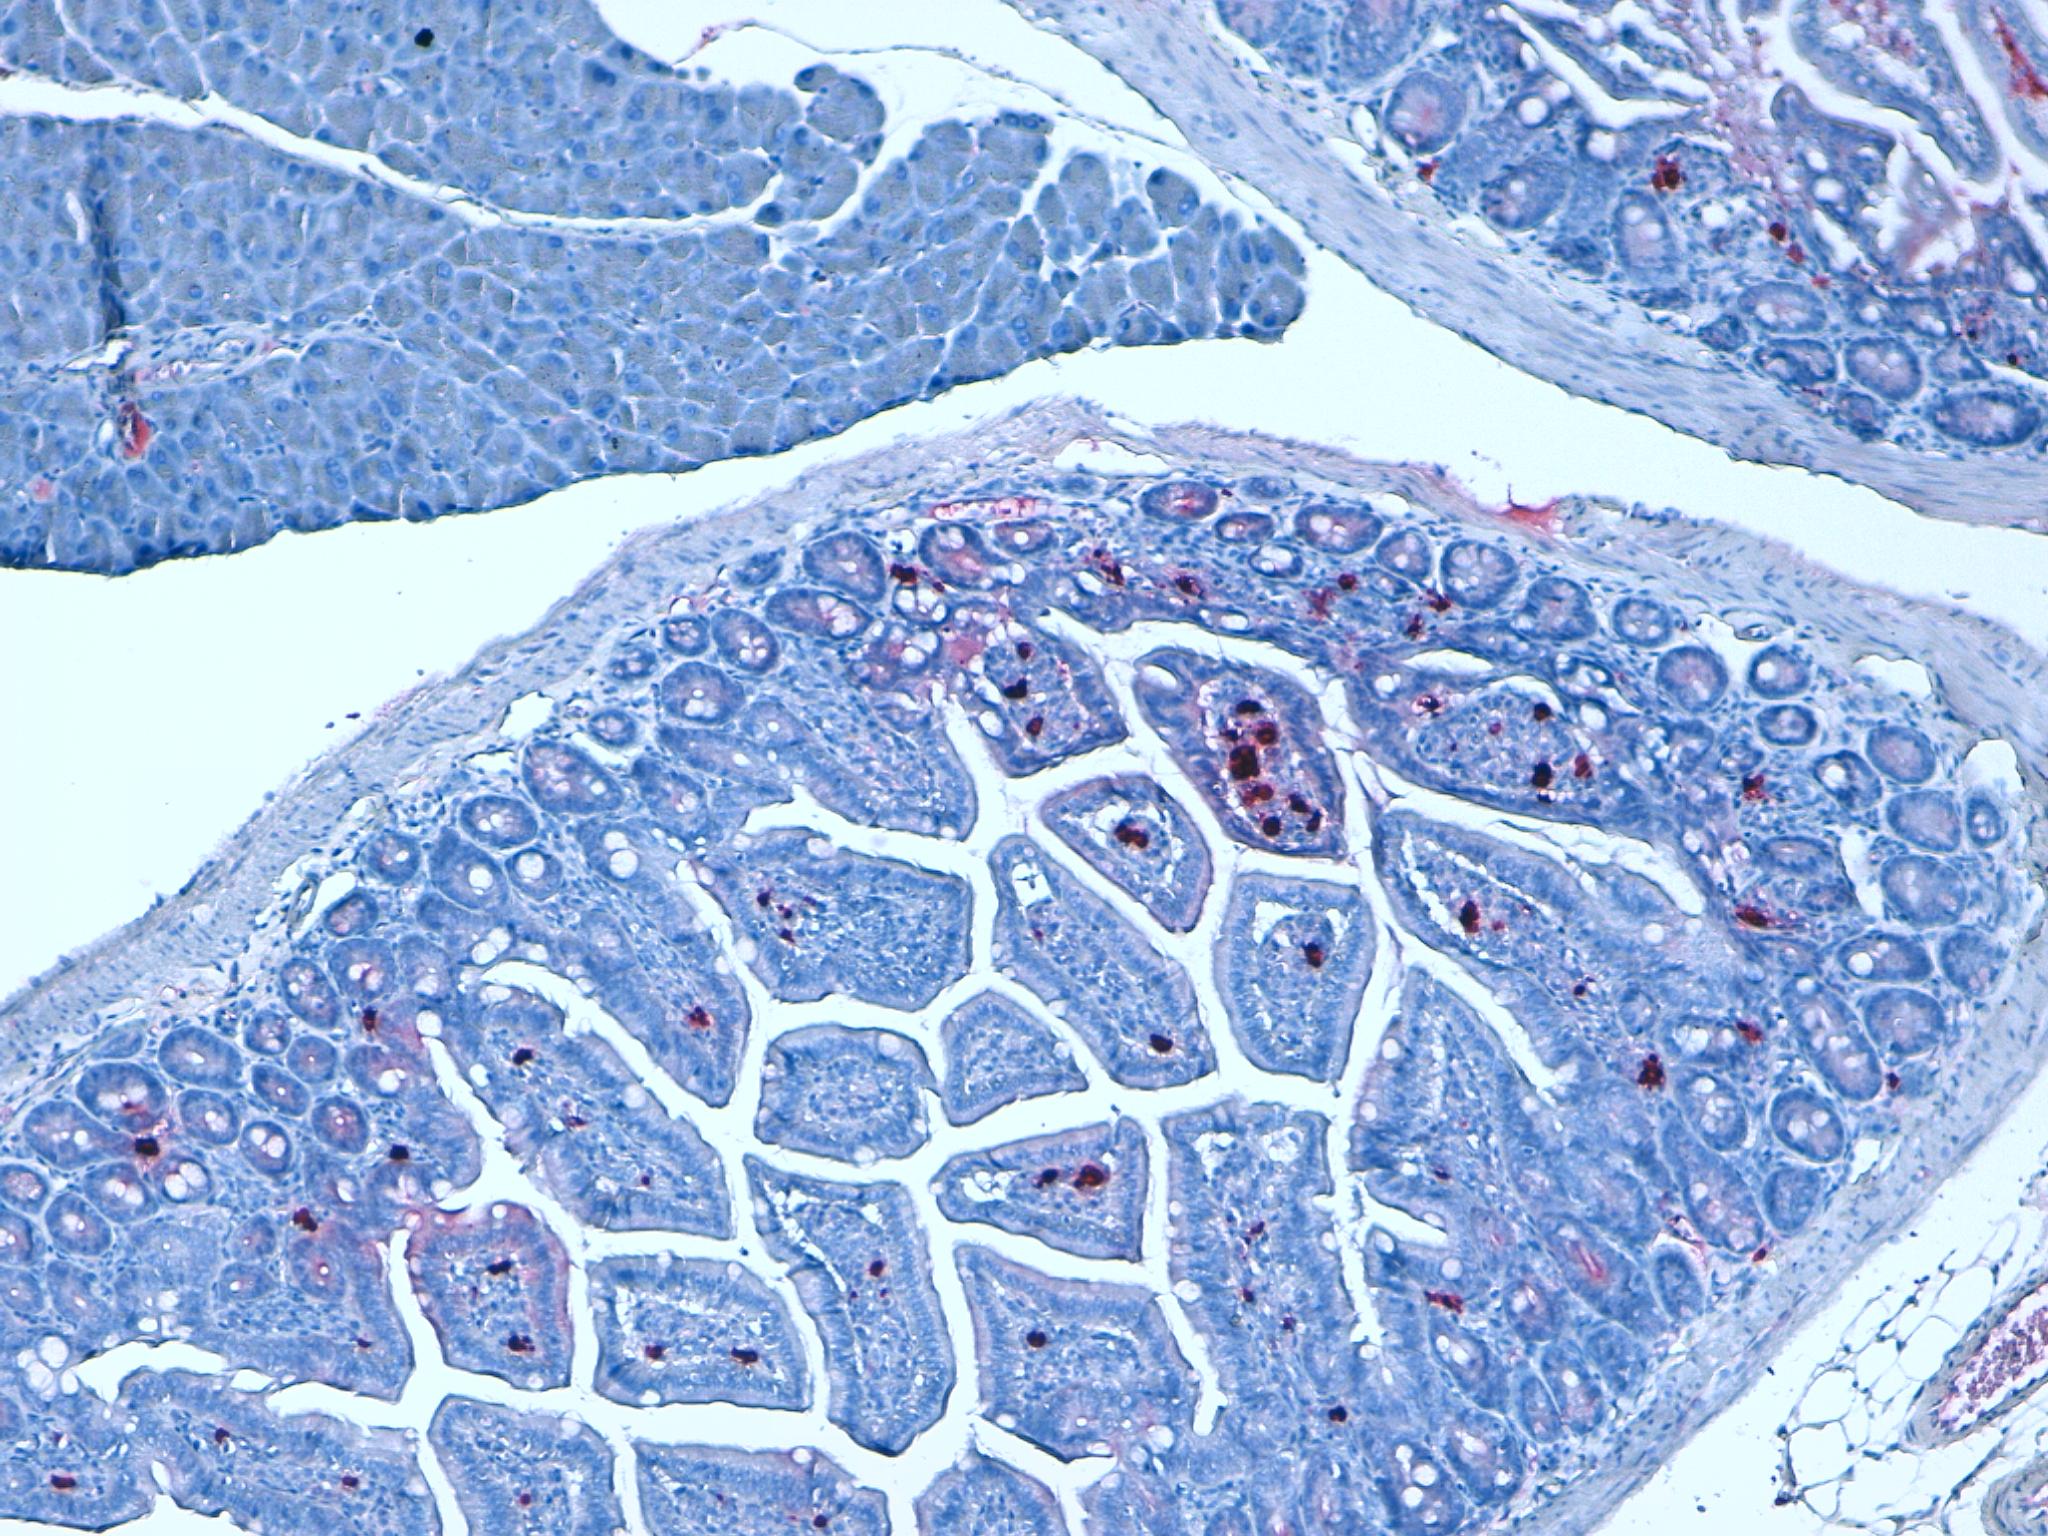

Multiplex IHC Staining: Mouse Colon, Colorazione HE

KI67 Mouse Intestine 20X

KI67 Mouse Intestine 10X

KI67 Mouse Colon 20X

Mouse Colon 20x ki67